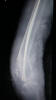

Fractura de diáfisis de húmero.